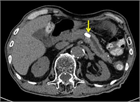

1. 膵管内の結石(膵石)を認めた場合と、膵全体に分布する複数かつびまん性の石灰化を認めた場合は慢性膵炎と診断できる(推奨度1)

1. 加齢現象に伴い膵石が観察される場合がある。

1. 石灰化を伴った膵腫瘍がまれに存在する。